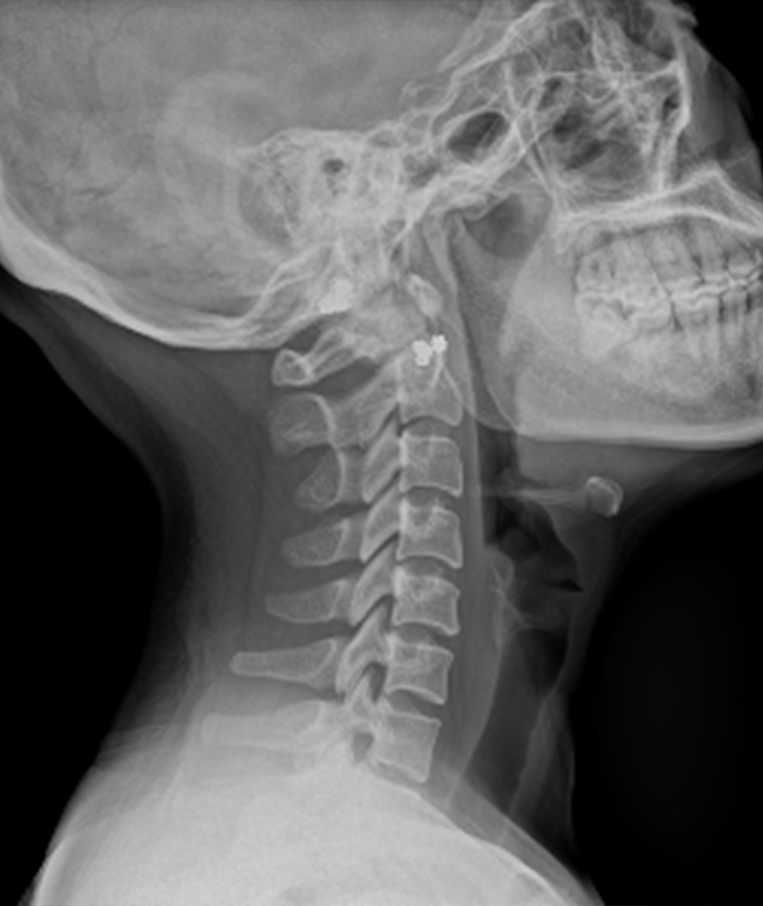

Clinical picture

臨床圖片